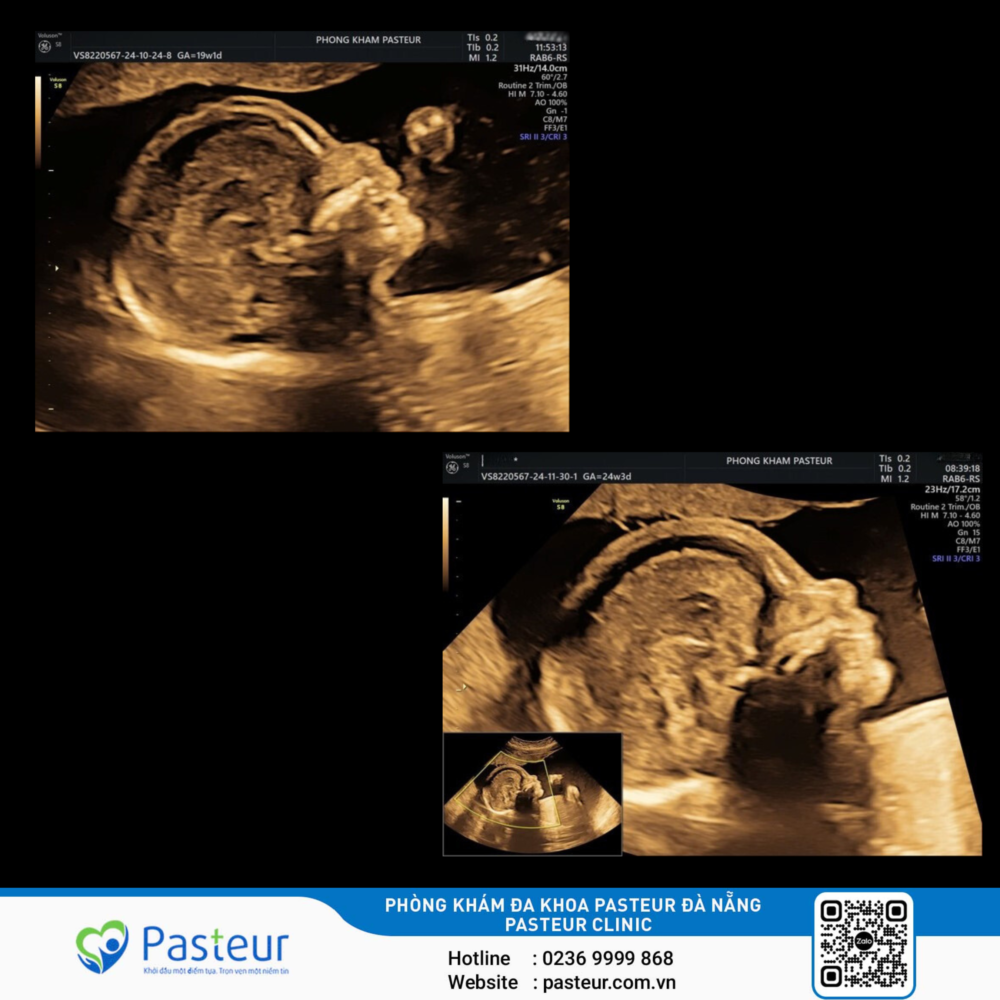

Thai phụ 37 tuổi, mang thai IVF (Thụ tinh trong ống nghiệm) lần 2 đến thăm khám tại Phòng khám đa khoa Pasteur thời điểm 15 tuần 5 ngày, siêu âm theo dõi thiểu sản xương mũi. Trước đó khám thai thời điểm 12 tuần tại nơi khác, xét nghiệm NIPT khảo sát nhiễm sắc thể 13,18,21 chưa phát hiện bất thường. Bệnh nhân được đề nghị chọc ối kiểm tra bất thường nhiễm sắc thể (NST) của thai nhi. Kết quả chọc ối cho thấy bất thường nhiễm sắc thể số 2: Lặp đoạn nhiễm sắc thể đoạn q32.1 – q32.2